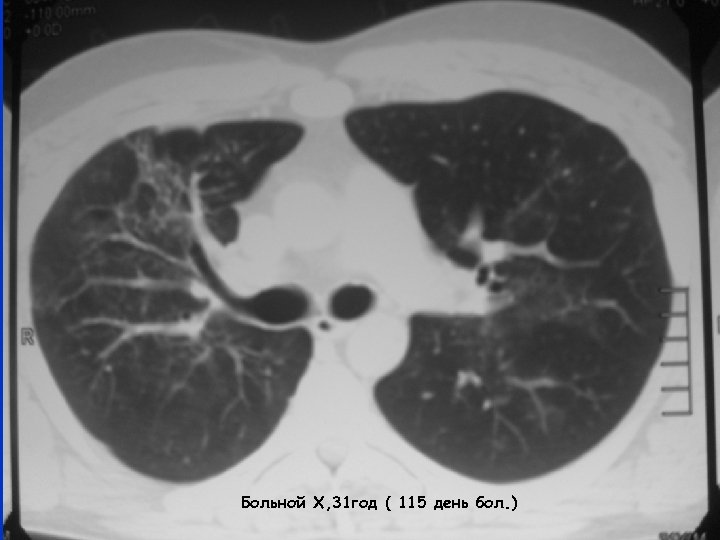

Больной Х, 31 год ( 115 день бол. )